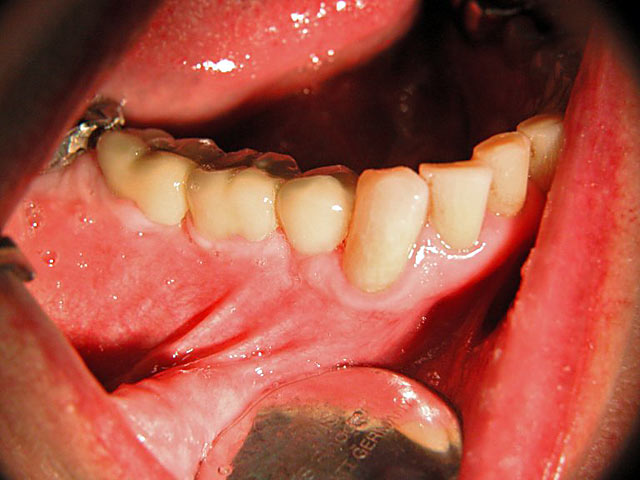

Kugelkopf-Implantation: